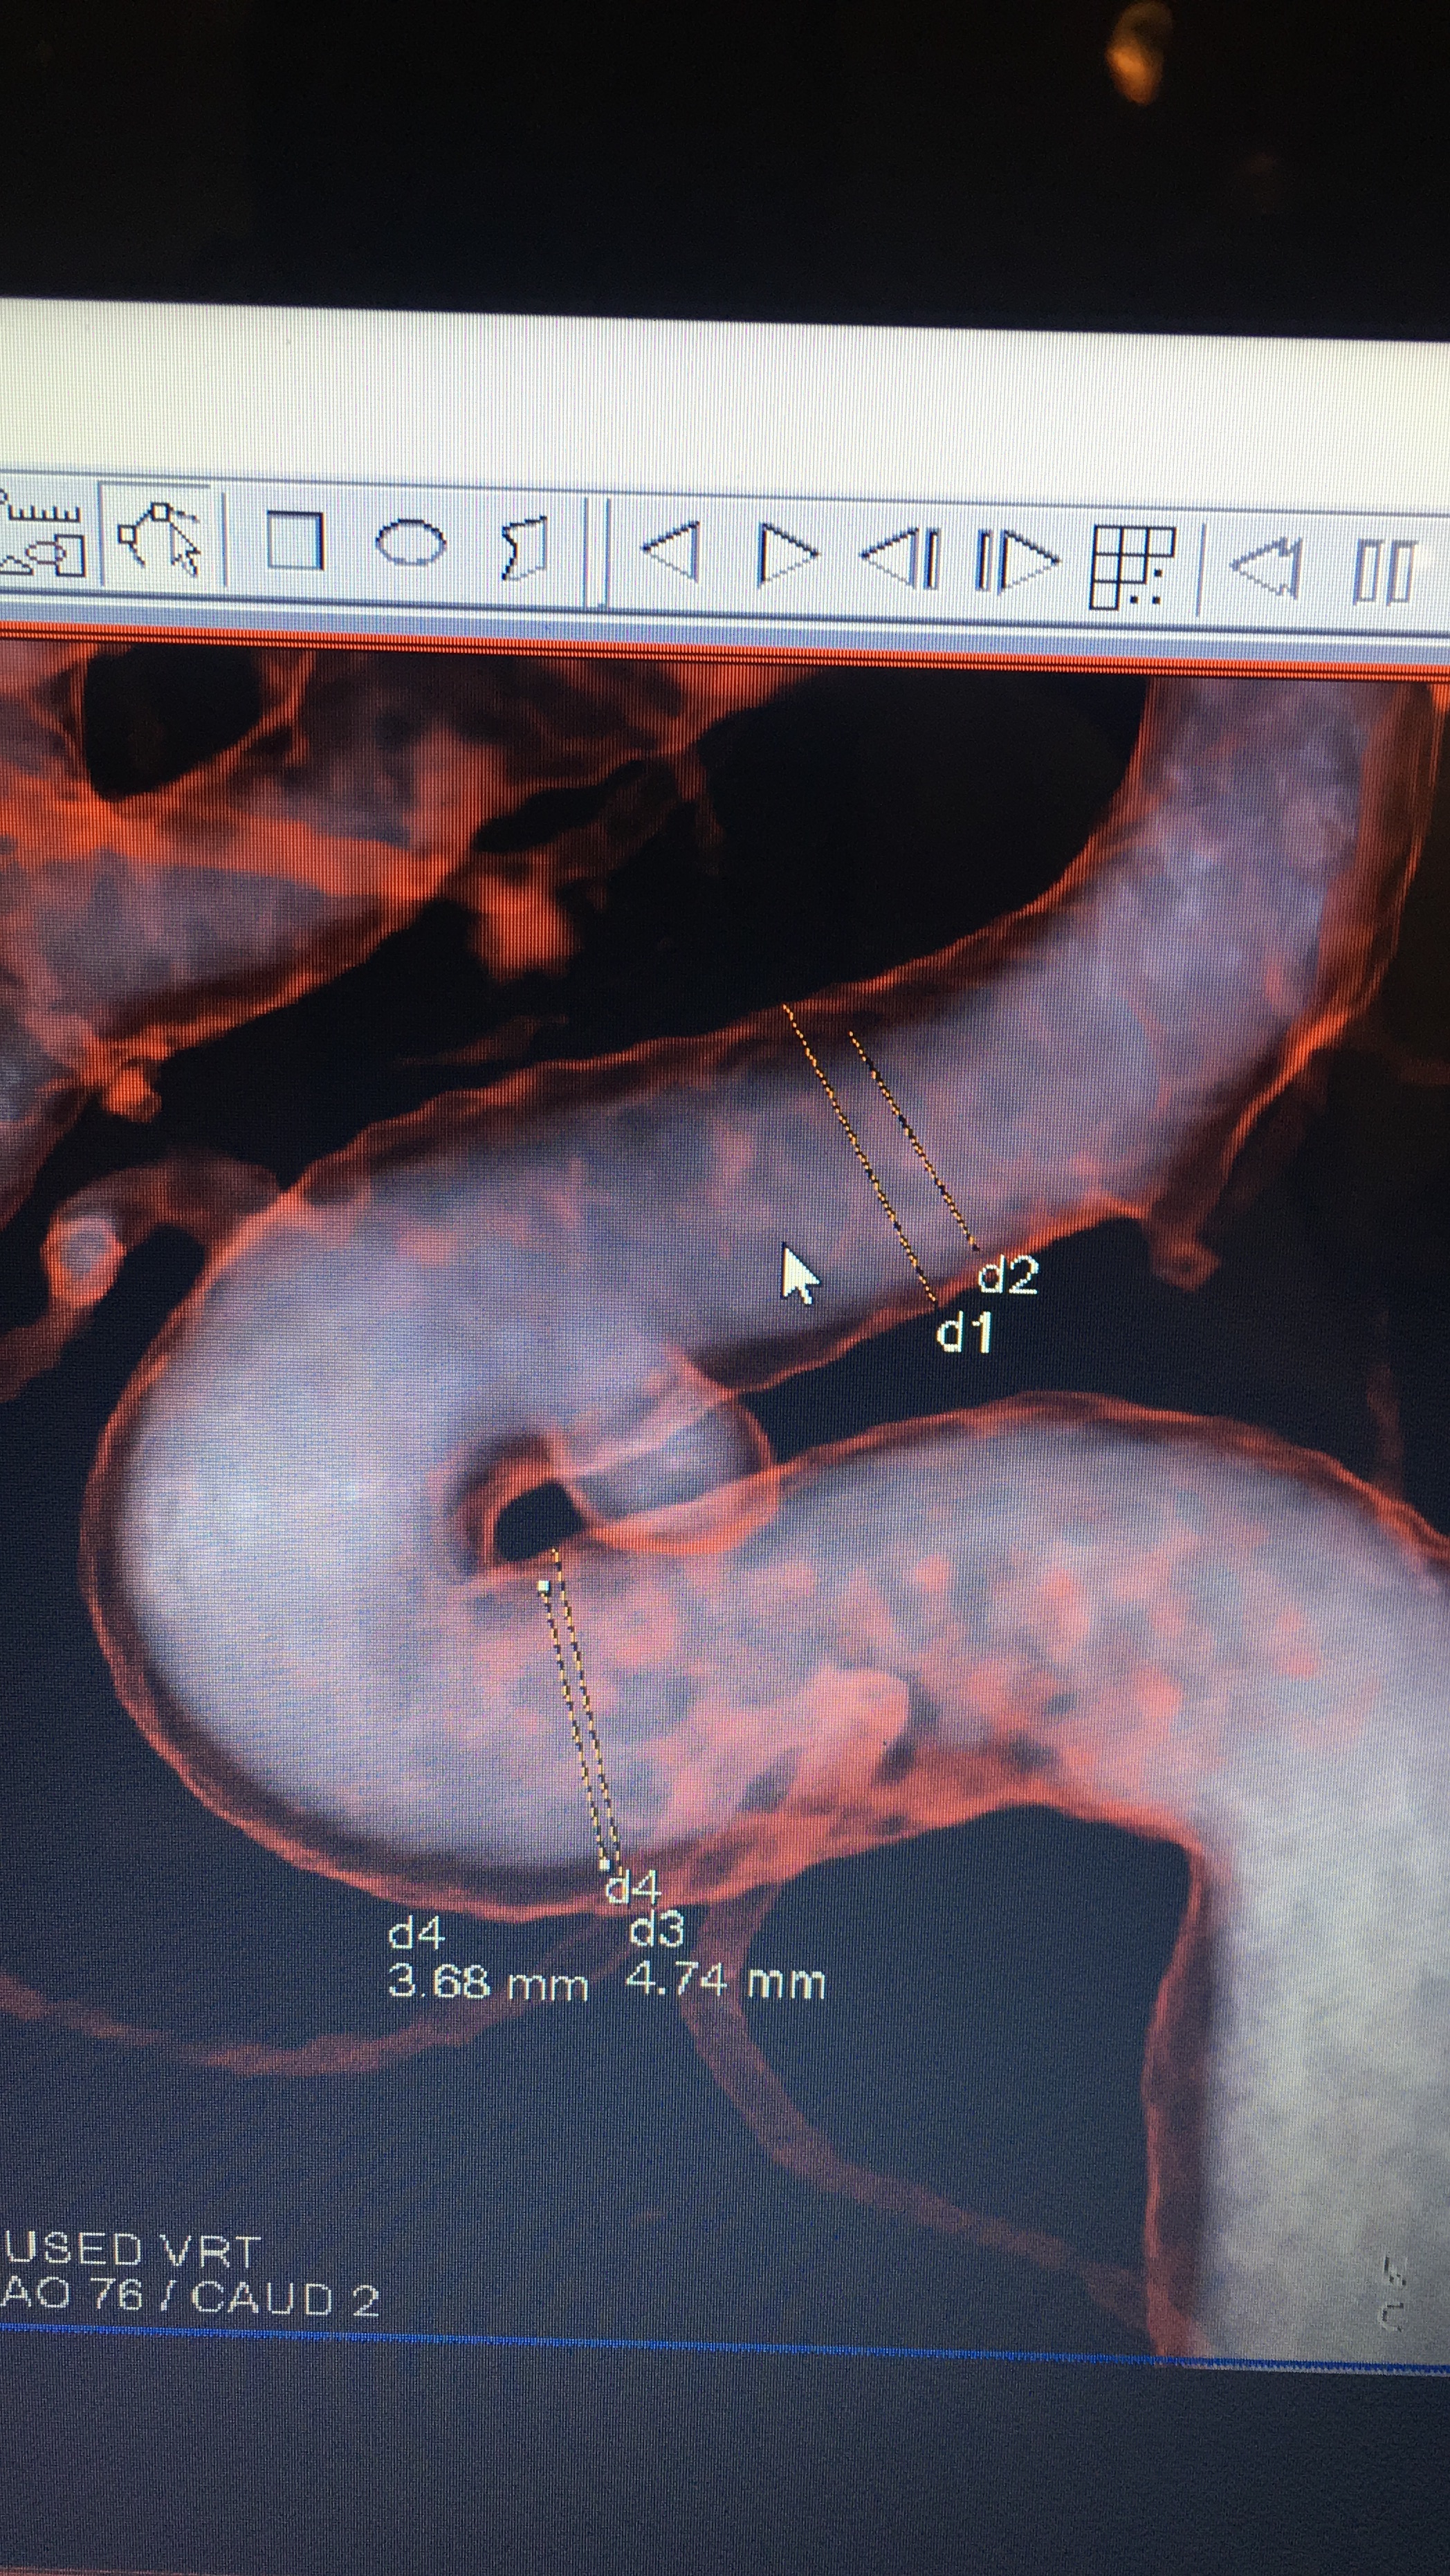

Today, we set date for Endovascular Treatment (Flow Diverter) for July 17th. My annie is 4 x 6.2 and due to the odd/rare shape and how it connect to the opthalmic artery that lead to my left eye, this is the best option FOR NOW! Clipping is not on the table right now as I am on Plavix and Aspirin and they don’t believe Cardiology will agree to stopping either one. I understand this as if they clip the annie, I may end up having a heart attack and Cardiology will likely say “hell no”. Next month will be a year since my heart stent, so there is a possibility I may have been coming off next month but there is no guarantee. On the other hand, since aspirin and Plavix is required for the flow diverter with a requirement for up to at least 6 months, there is a possibility the overlap can give Neurosurgery leverage to level off the aspirin and plavix (only for a couple of weeks for prep and until surgery is over) by that time and do the clipping IF the aneurysm is still active.

As I discussed with my Neurosurgeon, my goal is to control/manage this annie ASAP using the best treatment with the best outcome. He said with my annie there is a 0.5% chance of rupture over the next year. My annie as stated above is oddly shaped which is complicated in terms of risking vision loss. The annie itself is like a bubble but the neck is like a double bubble. It look like a hand is clasped over the annie and it is directly connected to the opthalmic artery. I told my husband that is God’s hand holding my annie! Coiling is off the table as if they filled it with coils, they could possibly fall out and if it clot that clot could easily travel in either direction and cause a stroke. I am comfortable with what we have planned as this is the best option for right now until we can do a clipping, if needed. He indicated there was a good chance the annie could shrink. He said, the primary goal of the flow diverter is to take the pressure off the annie which will ultimately reduce the chance of rupture. I am in good hands with some of the best doctors in the country and I trust their recommendation. Hubby took notes so if I forgot something I will post later once he type them out for me as I cannot read his “doctor” style writing. LOL